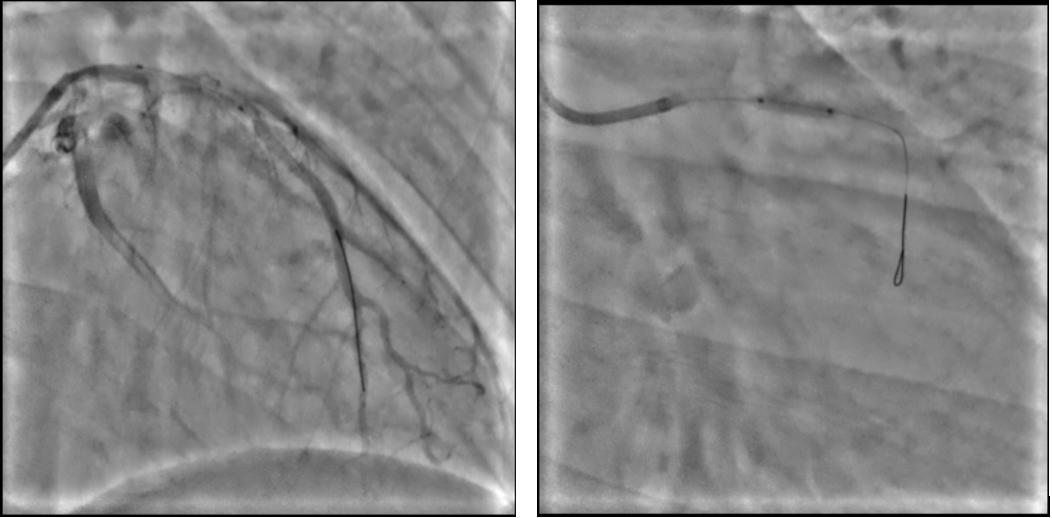

Xác định LAD là động mạch thủ phạm, kết quả IVUS xác nhận đường kính tham chiếu của mạch máu lớn (reference vessel diameter > 3.5 mm), gánh nặng mảng xơ vữa không quá lớn, và quan trọng là không có tình trạng vôi hóa nặng hay mảng bóc tách phức tạp sau khi nong bóng chuẩn bị. Những phát hiện này khẳng định đây là một tổn thương phù hợp lý tưởng cho chiến lược can thiệp chỉ bằng bóng phủ thuốc. Sau khi hút huyết khối, đội ngũ can thiệp quyết định sử dụng bóng phủ thuốc (DCB) kích thước 3.5x20mm để tái thông. Kết quả sau can thiệp cho thấy dòng chảy TIMI 3, mạch máu tái thông tốt, không bóc tách, không hẹp tồn lưu.

Hình ảnh 2a và 2b: Động mạch vành liên thất trước LAD sau khi tái thông, hút huyết khối. Hình ảnh sử dụng bóng phủ thuốc (DCB) kích thước 3.5x20mm để tái thông.